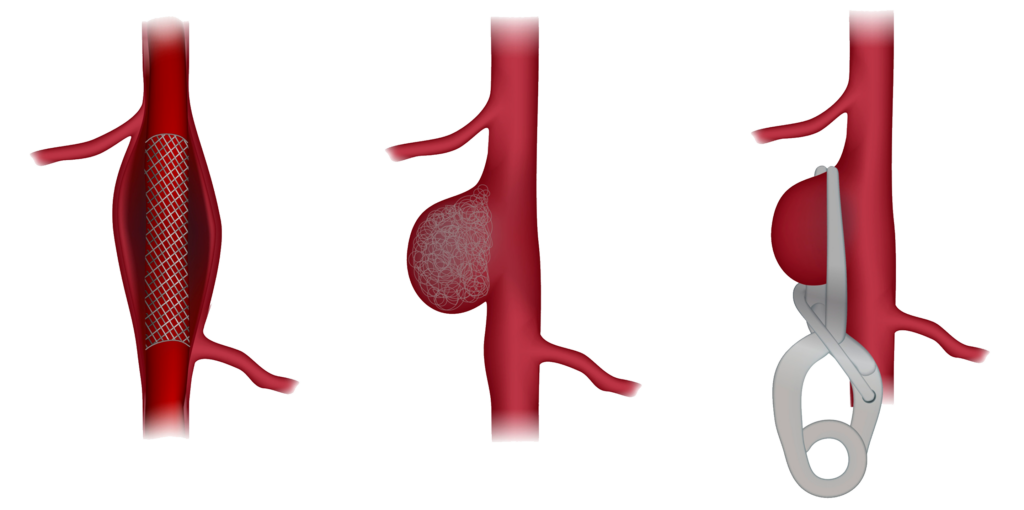

Điều trị can thiệp nội mạch

Điều trị can thiệp mạch được đặt ra đối với xuất huyết não có nguyên nhân thứ phát do bất thường mạch máu bao gồm phình động mạch não, dị dạng thông động-tĩnh mạch não, rò động tĩnh mạch màng cứng não.

Tại Bệnh viện Hoàn Mỹ Cửu Long đã triển khai tất cả các phương pháp điều trị đột quỵ cấp, bao gổm tiêu sợi huyết tĩnh mạch (r-TPA), can thiệp lấy huyết khối bằng dụng cụ trong điều trị nhồi máu não cấp; can thiệp nội mạch điều trị xuất huyết não do dị dạng mạch máu, túi phình mạch não…và được hiệu quả cao.